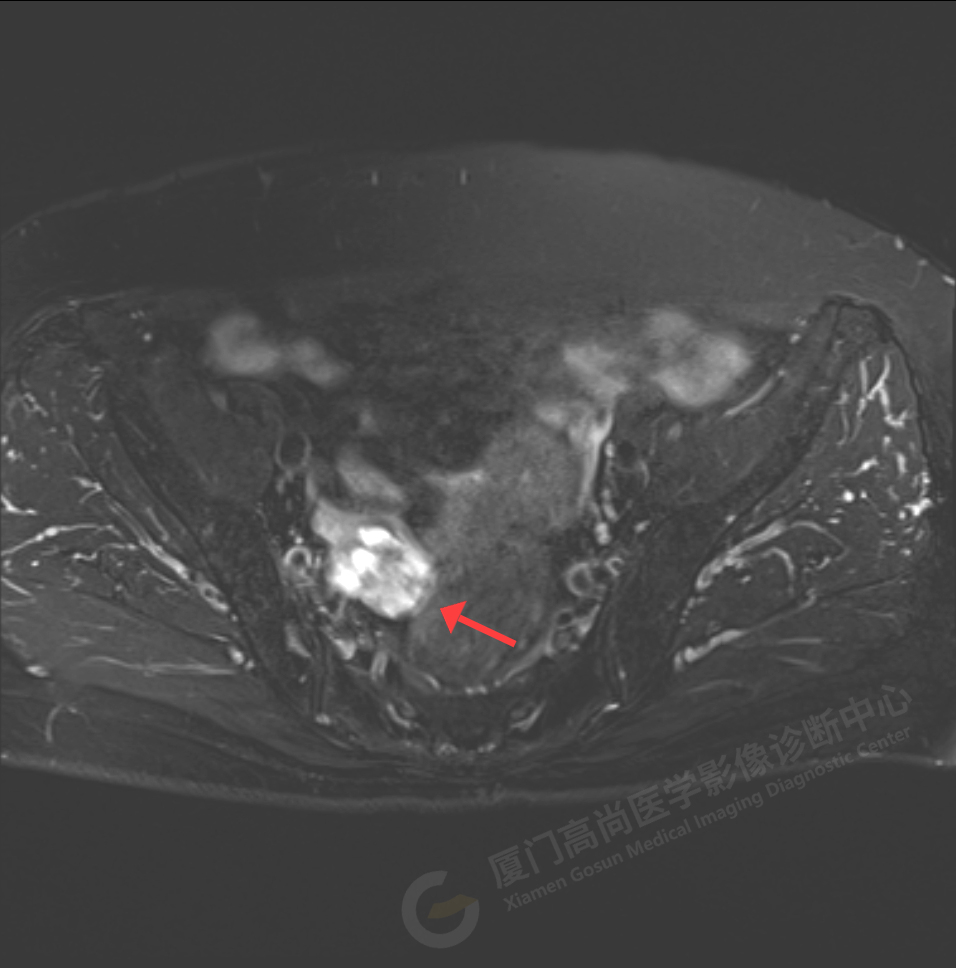

磁共振影像圖

我中心為陳阿姨安排了影像解讀及專家會(huì)診,經(jīng)過專家綜合分析,給出了初步診斷意見:右側(cè)附件區(qū)囊實(shí)性占位伴腫大淋巴結(jié),考慮卵巢來源惡性腫瘤,卵巢Ca可能性大。醫(yī)生建議盡快做進(jìn)一步的檢查及就診。

陳阿姨家人經(jīng)過多方打聽和聯(lián)系,陳阿姨于5月18日至廣東中山大學(xué)附屬腫瘤醫(yī)院會(huì)診及手術(shù),術(shù)后病理顯示:卵巢高級(jí)別漿液性癌2期,證實(shí)了高尚專家的判斷。